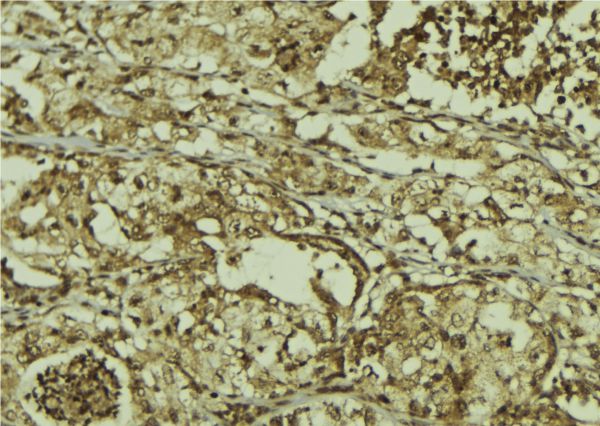

IHC (Immunohiostchemistry)

(AAA321421 at 1/100 staining Human breast cancer tissue by IHC-P. The sample was formaldehyde fixed and a heat mediated antigen retrieval step in citrate buffer was performed. The sample was then blocked and incubated with the antibody for 1.5 hours at 22 degree C. An HRP conjugated goat anti-rabbit antibody was used as the secondary.)